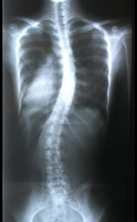

あらためまして、側弯症とは、

側弯症は、背骨が左右に曲がっているだけでなく、ねじれを伴っています。

前後面からレントゲン写真をとった場合に、脊柱が正面からみて左右に曲がっていて、ねじれを伴っている状態をいいます。